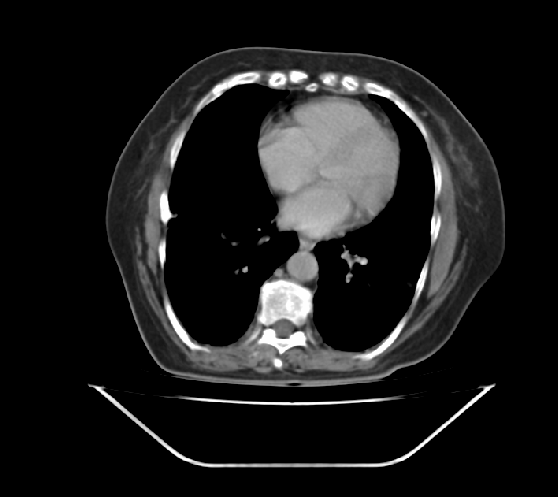

ist jemand unter Euch der sich auskennt mit CT Aufnahmen ?

Ich habe 3 Stück angehangen, sie stammen aus einem CT der Abdomen.

Möglich das es eine Serie eines Querschnitts darstellt Bild 1 zeigt den Start,Bild 2 eines aus den mittleren Aufnahmnen und Bild 3 das letzte dieser CT Serie.

Da ganz gezielt auf ein und die gleiche Stelle gehalten wurde mit sagenhaften über 80 Einzelaufnahmen interessiert mich brennend um die Darstellung welches Organges es sich bei diesen Aufnahmen handelt und ob darauf etwas bedenkliches eingekreist wurde.

Herzlichen dank für die Hilfe,falls jemand es einordnen kann. Mir ist die Antwort darauf so wichtig weil es sich um Aufnahmen meiner Mutter handelt die nicht mehr unter uns ist.